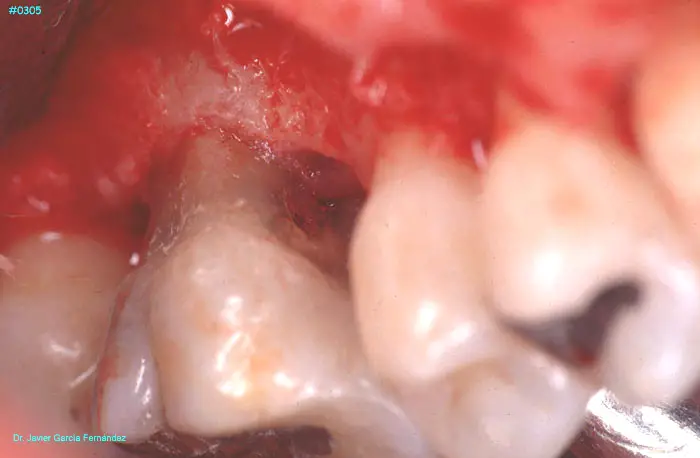

ATLAS DE CIRUGIA PERIODONTAL